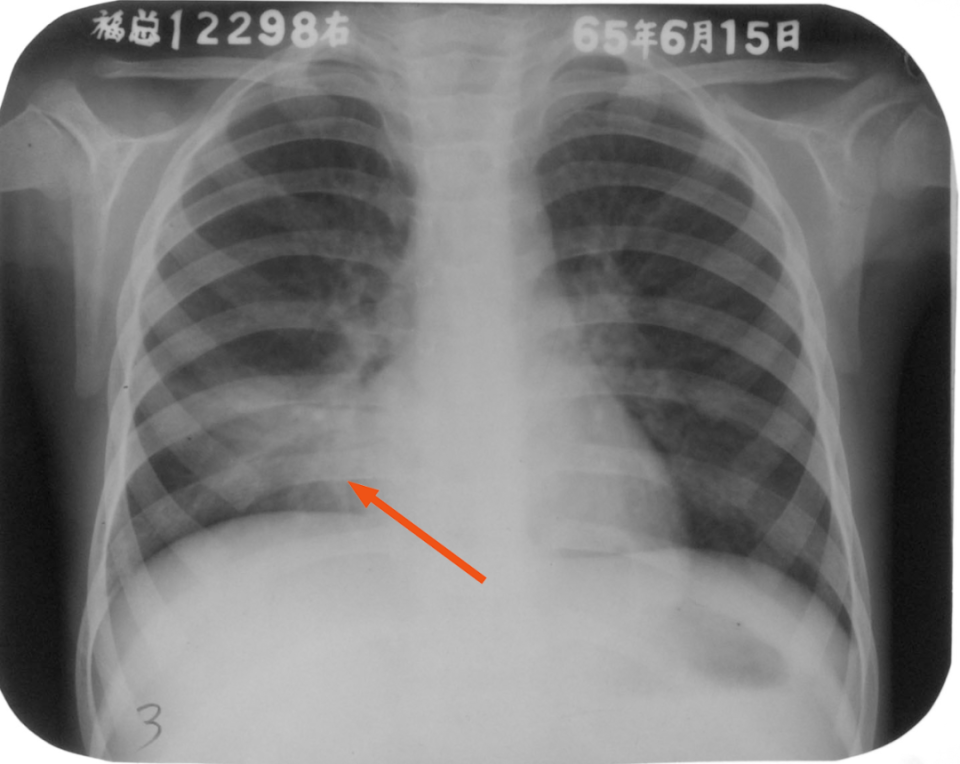

右肺中叶大叶性肺炎正侧位

图片

胸部正侧位片:右肺中叶见片状致密影,边缘模糊,局部呈剪影样改变(红圈所示)

右肺中叶大叶性炎症

胸部正位片:右肺中叶见片状致密影,边缘模糊(箭头所示)

右肺下叶后基底段大叶性炎症

胸部正侧位片:右肺下叶见片状致密影,右侧膈面及邻近胸廓边缘模糊(箭头所示),心缘清楚